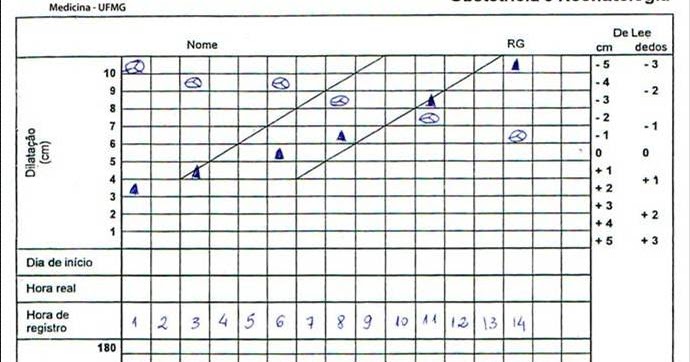

Padrões de dilatação cervical em mulheres “de baixo risco” com trabalho de parto espontâneo e resultados perinatais normais: uma revisão sistemática

Cervical dilatation patterns of ‘low‐risk’ women with spontaneous labour and normal perinatal outcomes: a systematic review OT Oladapo,…